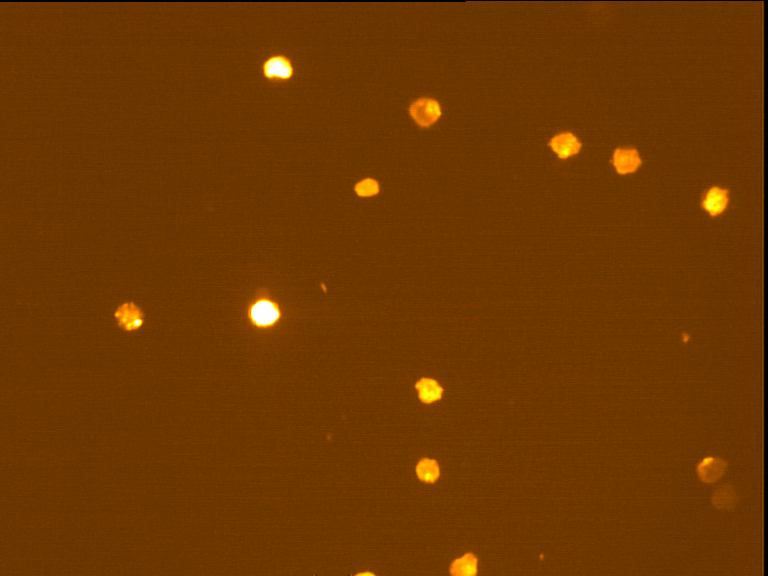

Fig. 4 through 6 show the morphological features of Raji cell sub-lines exposed to DOX, indomethacin, or verapamil. Some of the reversal agents significantly increased the frequency of apoptotic cells compared with control cells. Thus, the P-gp reversal agents were able to overcome apoptotic resistance in the NHL cell-line model. Apoptotic cells in the controls contributed approximately 10% of the whole population (i. e., 61/600 x 100 = 10.16% for TK+ and 69/600 x 100 = 11.5% for TK-). After exposure to the P-gp reversal agents, apoptic cells increased to 22.3% with indomethacin and to 43% with doxorubicin in TK+ cells. In TK- cells, apoptic cells increased from 11.5% to 26.8% and 75.7% with indomethacin and doxorubicin, respectively.

Fig. 6: Morphological features of Raji TK- cells after treatment with indomethacin (1), verapamil (2), and DOX (3). In each row, left images show intact cells, middle images show apoptotic cells, and right images show necrotic cells as they appeared under the microscope X 200